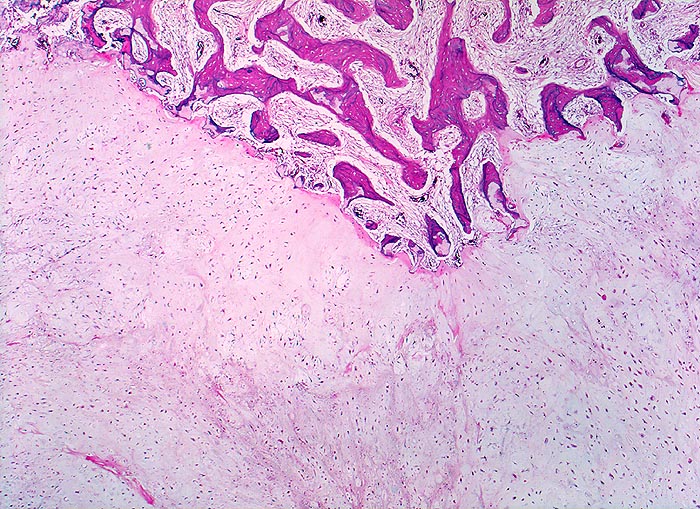

Morphologische Merkmale:

• Von Periost bedeckter kortikaler Knochen.

• Zellarmer lobulierter Knorpeltumor.

• Destruktive Tumorinfiltration des spongiösen und kortikalen Knochens.

• Der maligne Knorpel mit reichlich heller chondroider Matrix gleicht nicht neoplastischem hyalinem Knorpelgewebe.

• Im Vergleich zu normalem Knorpel leicht erhöhte Zellularität.

• In Höhlen liegende Tumorzellen mit hyperchromatischen, leicht vergrösserten Kernen.